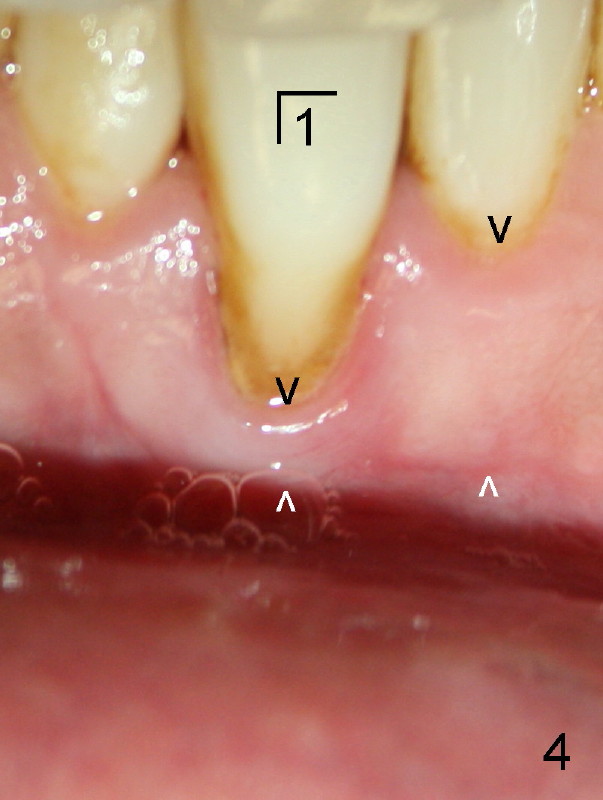

Forty-year-old man had ortho with extraction in his teens (Fig.1,2: B: bicuspid). Without wearing retainers, relapse occurs, particularly in the lower anterior. The lower left central incisor shifts labially with gingival recession (Fig.2,3). The attached gingiva is narrow for this incisor as compared to that of the neighboring tooth (Fig.4 between arrowheads). Although there is abundance of calculus, bone loss is mild to moderate (Fig.5-7). Scaling and root planing was finished today with schedule of perio maintenance every 3 months.

Both arches are narrow (Fig.1,2). Will be there space to move the lower left central lingually? Once the tooth is in normal position, gingival graft is performed to correct recession.